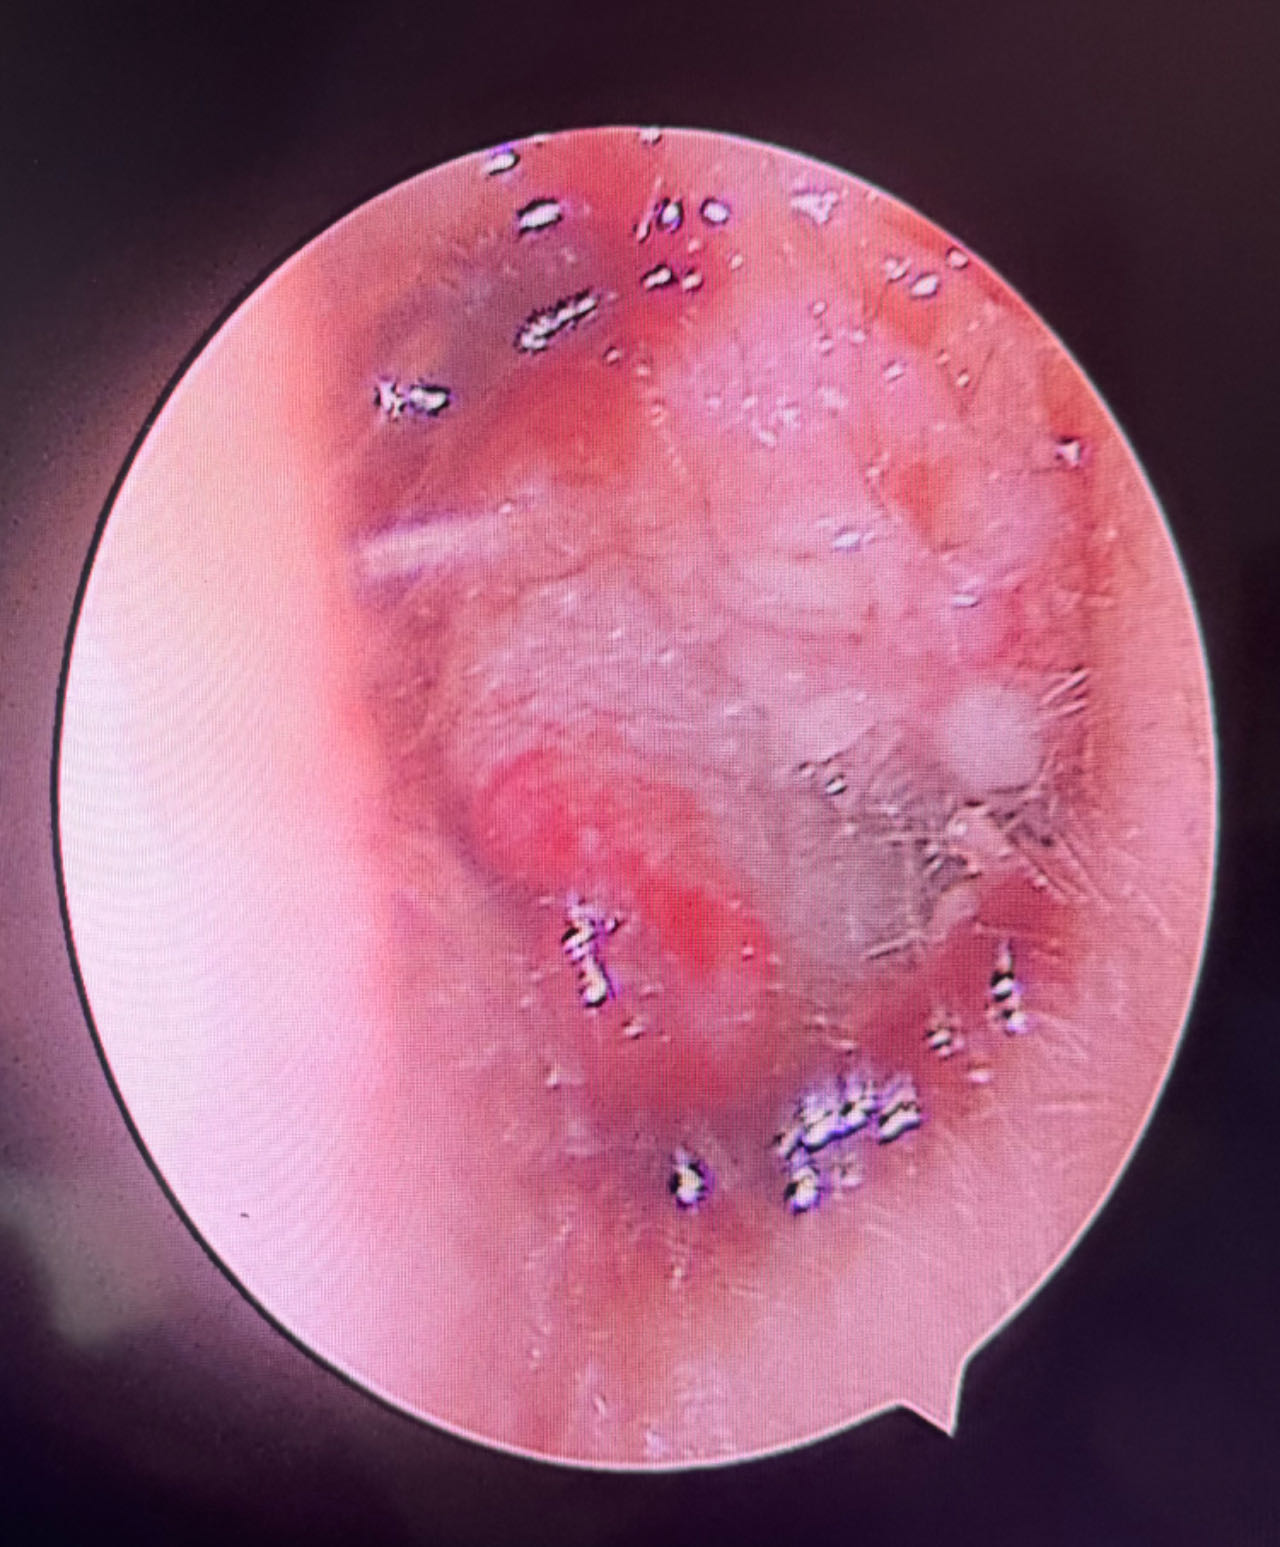

检查显示彤彤右耳道轻微红肿,左耳道内可见大量血液脓性分泌物。于是,对彤彤进行了左耳道清洗,清洗后显示外耳道壁可见多处脓肿、局部破溃、鼓膜完整。